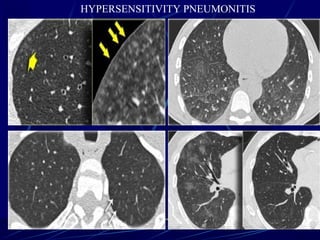

Centrilobular distribution

Hypersensitivity pneumonitis

Hypersensitivity pneumonitis (HP) (also known as extrinsic allergic

alveolitis) represents a group of pulmonary disorders mediated by inflammatory

reaction to inhalation of an allergen. These may be organic or inorganic

particles (microbes, animal or plant proteins, and certain chemicals) that form

haptens by sensitised individuals.

Depending on the type of precipitant, numerous other more precipitant specific terms

have been used such as:

bird fancier's lung: pigeon fancier's lung

farmer's lung

Cheese workerโ€™s lung

Mushroom workerโ€™s lung

Malt workerโ€™s lung

Maple bark disease

hot tub lung

organic chemicals such as isocyanates found in paint hardeners

from immunosuppresants used in organ transplantation: e.g. sirolimus/everolimus 8